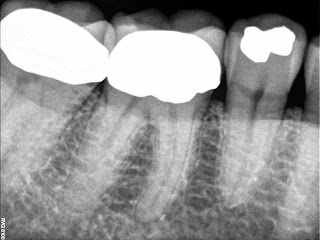

Root Canal Lower Molar First

Vital. Normal anatomy

All 3 canals had apical curvatures that rotaries wouldn’t curve around so had to hand file. They may have been stuck in a ledge formed from my overaggressive use of SX to open coronal though also. either way this took 2 hours and should have been about 1 hour.